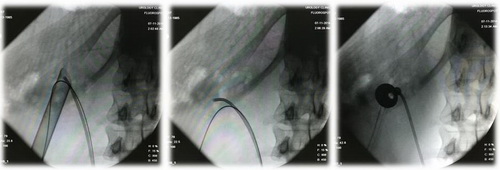

Рис. Ультразвуковое исследование.

Рис. Рентгенологические этапы операции.